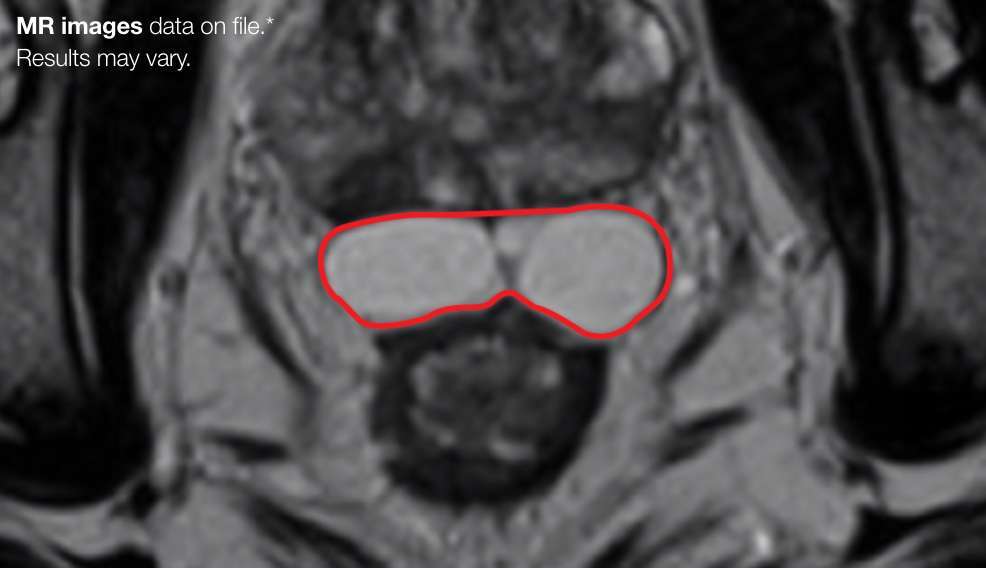

PATIENT EXAMPLE SHOWING

STABLE SEPARATION DURING RESORPTION

Results may vary.